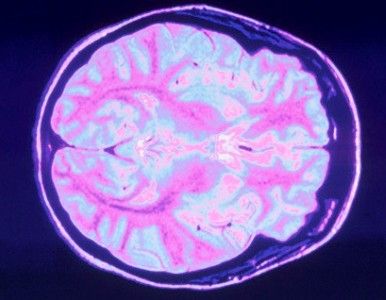

CIENTÍFICOS CREAN UNA PRÓTESIS PARA LEER LA MENTE

Fisiólogos estadounidenses crearon una tecnología que permite registrar la actividad eléctrica cerebral, que desarrolla una